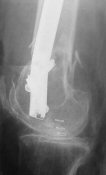

Attached are few examples from our Hospital:

B. Fixation loosening: distal cutting of the nail, non-unions do happen (cases attached).

Locking Plating has more distal screws than any nail, fixed angles and provides much better fixation, especially in osteoporotic bone.

Dr. Melamed: Principles for LISS and LCP are the same, again - LISS has outrigger helping for more percutaneous technique.